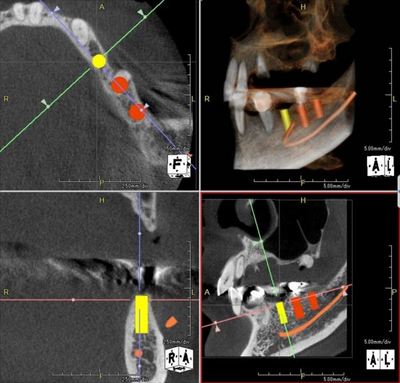

CTシミュレーションを事前に行います。

模型とCTデータを重ね合わせて埋入ポジションを決定します。